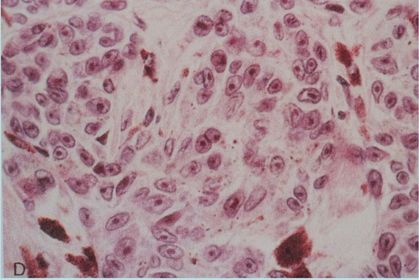

Diagnóstico e Características MELANOMA Melanócitos atípicos, núcleo grande, nucléolo evidente.